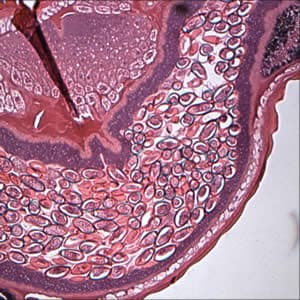

A 27-year-old woman who had been working in Laos, Thailand, and Vietnam for one and a half years was visiting relatives in the U.S. While she was in the U.S., she visited a physician for recurring abdominal discomfort, bloating, and frequent bowel movements that she had experienced over the last two months.